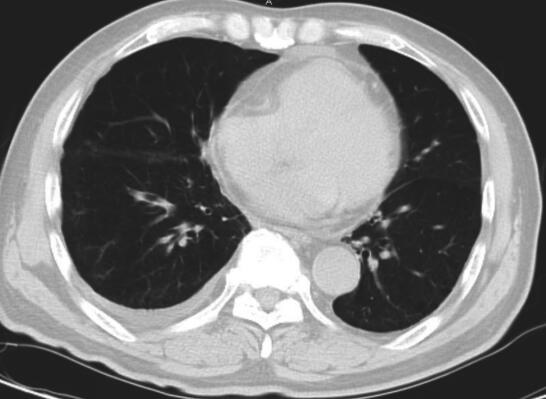

2014年5月2日出现发热、肝功能损伤,停抗结核药。完善胸部CT检查发现右侧胸腔积液,给予抽液检查,胸腔积液常规:颜色:黄色,透明度:清澈,蛋白定性:阴性,白细胞计数:2.6,多个核细胞:5%,单个核细胞:95%。于2014年5月12日调整抗结核药物为HRE。4个月后复查胸部CT(图3和图4)见右肺病灶明显吸收,纵隔淋巴结未见肿大。

图3 2014年9月17日胸部CT

肺窗见右肺下叶病灶吸收